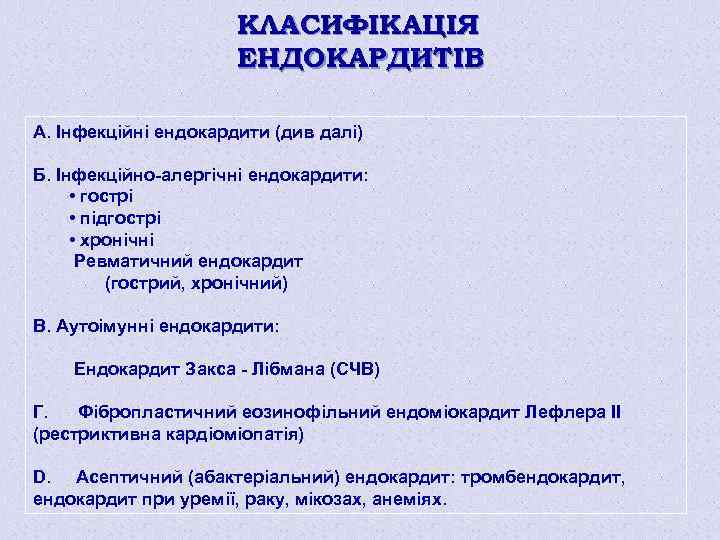

КЛАСИФІКАЦІЯ ЕНДОКАРДИТІВ А. Інфекційні ендокардити (див далі) Б. Інфекційно-алергічні ендокардити: • гострі • підгострі • хронічні Ревматичний ендокардит (гострий, хронічний) В. Аутоімунні ендокардити: Ендокардит Закса - Лібмана (СЧВ) Г. Фібропластичний еозинофільний ендоміокардит Лефлера ІІ (рестриктивна кардіоміопатія) D. Асептичний (абактеріальний) ендокардит: тромбендокардит, ендокардит при уремії, раку, мікозах, анеміях.